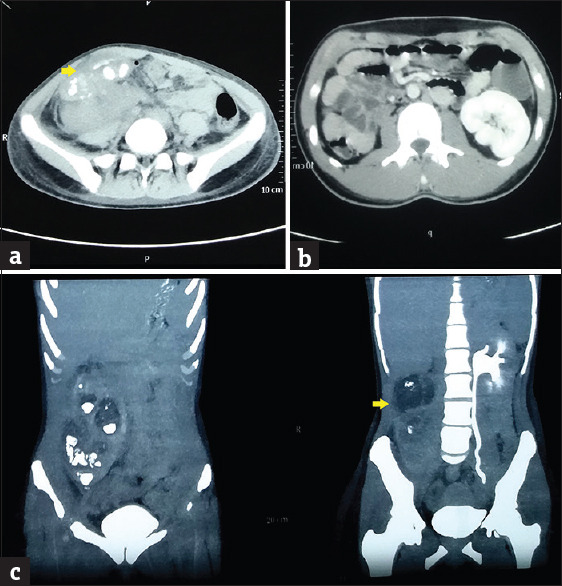

Ectopic kidney is a congenital anomaly of renal position, which is commonly asymptomatic. Symptoms arising from pelvic kidneys can closely mimic pathological processes of nearby organs and vice versa. We report an 18-year-old girl who presented with acute onset of a painful lump in the right iliac fossa. Although the clinical features mimicked an appendicular abscess, the judicious use of cross-sectional imaging aided in the proper diagnosis. Pyonephrosis of a right-sided lumbar kidney was confirmed on further imaging and nephrectomy was performed. This case has been presented to highlight the significance of renal imaging in patients suspected of an appendicular abscess.